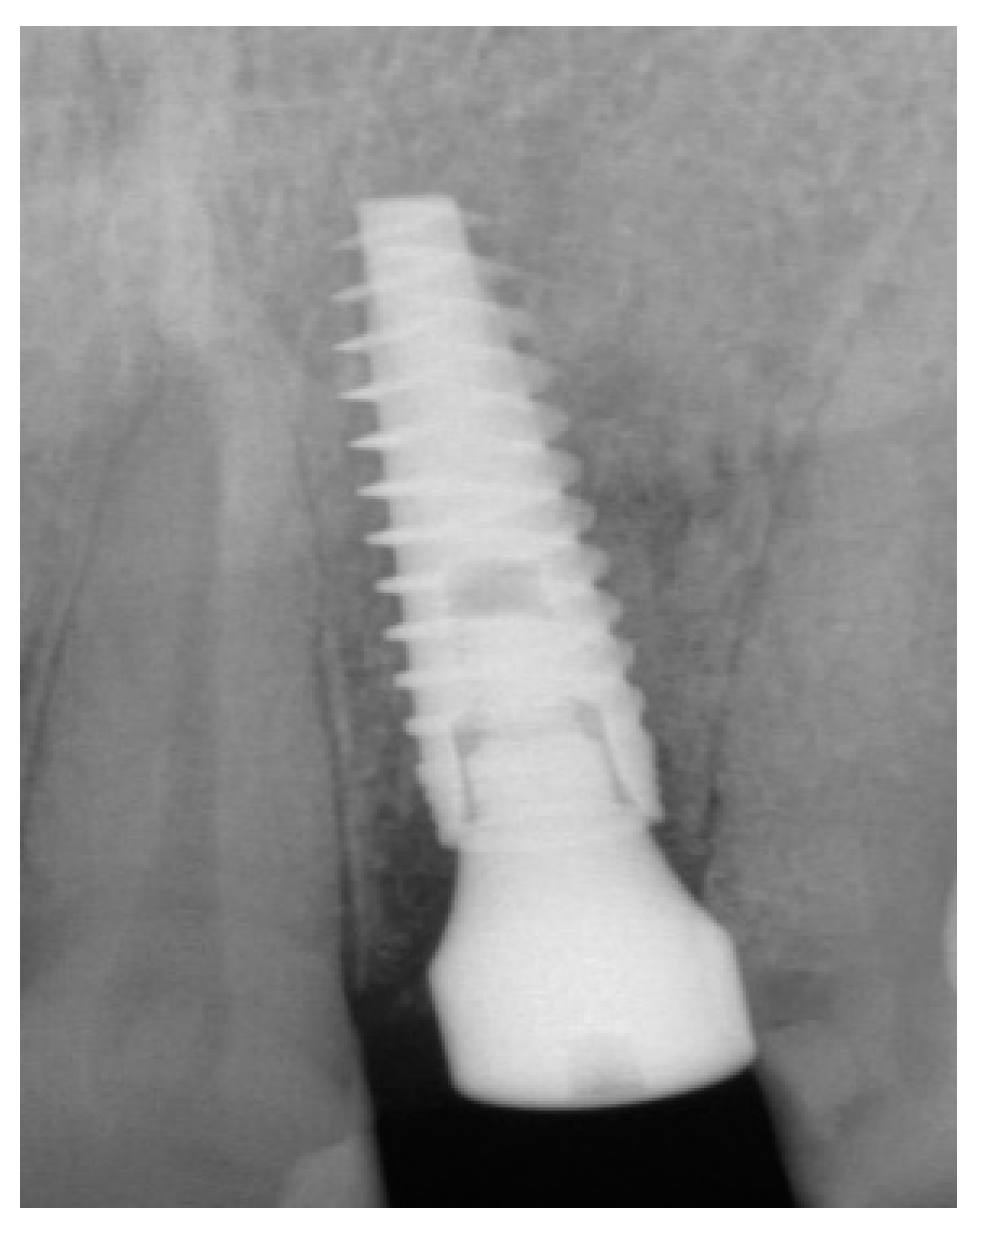

The surgical protocol was followed as described for the previous patient. Likewise, an implant was placed, followed by the placement of bone graft material over the defect and covered with a resorbable membrane. Six months later, the implant was fully intergraded (Figure 10), and the soft tissue appeared to be within normal limits (Figure 11). The implant was restored with a ceramic zirconia crown. Figure 12 presents the patient three years after treatment.

Figure 10.

Radiograph of the lateral incisor.

Figure 11.

Occlusal view of implant site before final restoration.